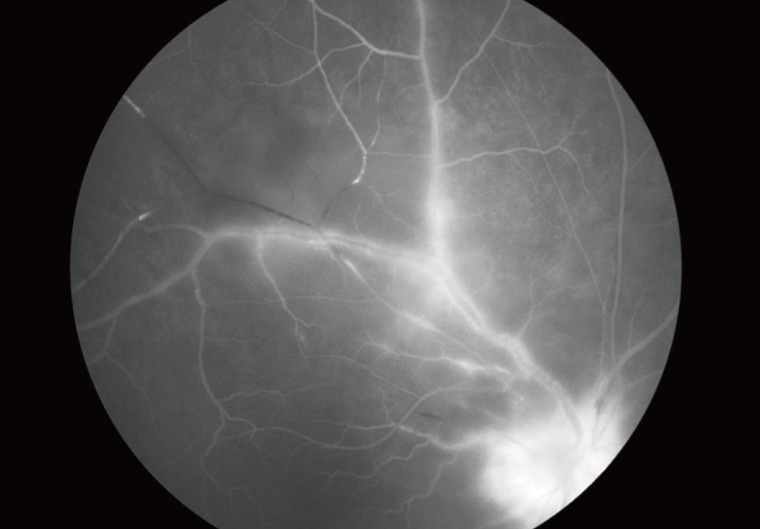

The complications of ocular toxoplasmosis include chronic iridocyclitis, cataract formation, secondary glaucoma, band keratopathy, cystoid macular edema, retinal detachment (Fig. 4), and optic atrophy secondary to optic nerve involvement. Choroidal neovascularization has been described as a late complication of ocular toxoplasmosis (Fig. 5). Other retinal vascular lesions, described as complicating toxoplasmosis, include branch artery occlusion, periphlebitis, and toxoplasmic scleritis.